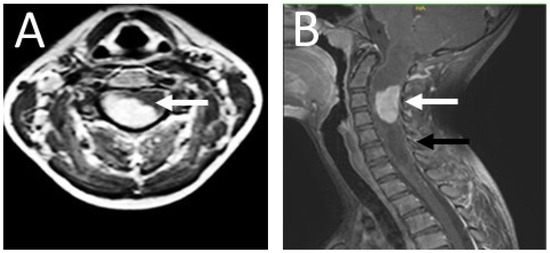

2. Case Presentation